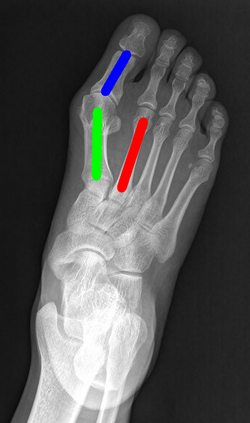

Angular measurements is essential to make a resonable treatment for Hallux valgus (HV), a common forefoot deformity. However, it still depends on manual labeling and measurement, which is time-consuming and sometimes unreliable. Automating this process is a thing of concern. However, it lack of dataset and the keypoints based method which made a great success in pose estimation is not suitable for this field.To solve the problems, we made a dataset and developed an algorithm based on deep learning and linear regression. It shows great fitting ability to the ground truth.